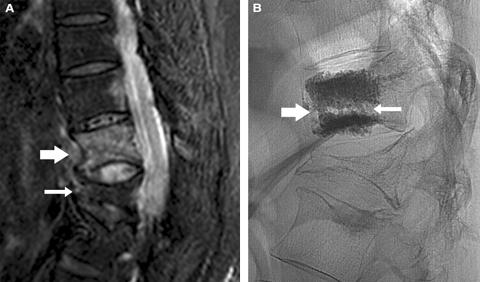

Most of the fractures that we treat are not simple crush fractures, but have more complex architecture. These more complex fracture types are associated with more severe pain. Axial transections of the vertebral body (Box 1) seem far more painful than simple crush fractures. Acute fractures adjacent to old, deformed, healed fractures are also associated with amplified pain, presumably because there is abnormal biomechanical stress through the fracture line. Osteonecrotic fracture clefts develop in some patients with osteoporosis (Box 2), and are often associated with severe and more prolonged pain. We observe that vertebroplasty provides early pain relief and mobilisation in patients struggling to cope in the acute situation.

Vertebroplasty is operator dependant and proper technique is very important. The technique as described in the Buchbinder et al trial3 mandates the use of 13-gauge needles and 1 mL syringes to inject the bone cement. The average injected volume was 2.8 mL of cement which is, in our experience, too little to adequately stabilise most vertebral fractures. In our practice, lumbar fractures usually require cement volumes of up to 10 mL per treated level, necessitating the use of 11-gauge needles and more modern injecting systems. The cement distribution must be sufficient to provide internal fixation to all segments of the vertebral body, or the procedure will not be effective (Box 2). These technical failings are central problems of the study, and could also explain the relatively poor outcomes of the trial’s vertebroplasty group.